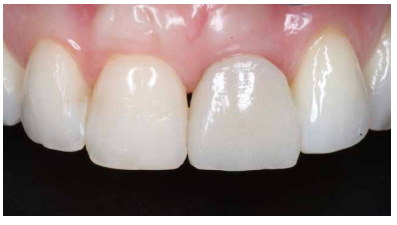

Para la realización del perfil de emergencia (PE), se determinó la posición ideal del margen ginigival que coincidiría con la disposición de la línea cervical (unión amelo-cementaria) del ICSI (Figuras 10-13B).

A los 4 meses se evidenció una correcta estabilidad del IOI fruto de un correcto proceso de osteointegración. Respecto a los tejidos blandos, se podía observar una disminución del volumen de la papila interdental (Figura 21). Dada la ausencia de signos y síntomas y la correcta osteointegración del IOI, se realizó la modificación del perfil subcrítico con el fin mejorar la disposición del tejido blando gingival y favorecer la recuperación de dicha papila (Figuras 22 y 23).

A los 6 meses se puede observar una correcta disposición de los tejidos blandos, así como la estabilidad de estos en el tiempo debido al manejo de los mismos a través de la prótesis provisional (Figura 24). Se realizó además un control radiológico para conocer el estado de los tejidos duros (Figura 25).

Dada la correcta evolución del caso a los 6 meses, se llevó a cabo el registro de la posición del IOI y del perfil de emergencia mediante un transfer individualizado con el fin de replicar de forma fiel y detallada la arquitectura gingival (Figuras 26 y 27). Finalmente se colocó la prótesis fija final atornillada al IOI a los 7 meses del inicio del tratamiento (Figuras 28 y 29).